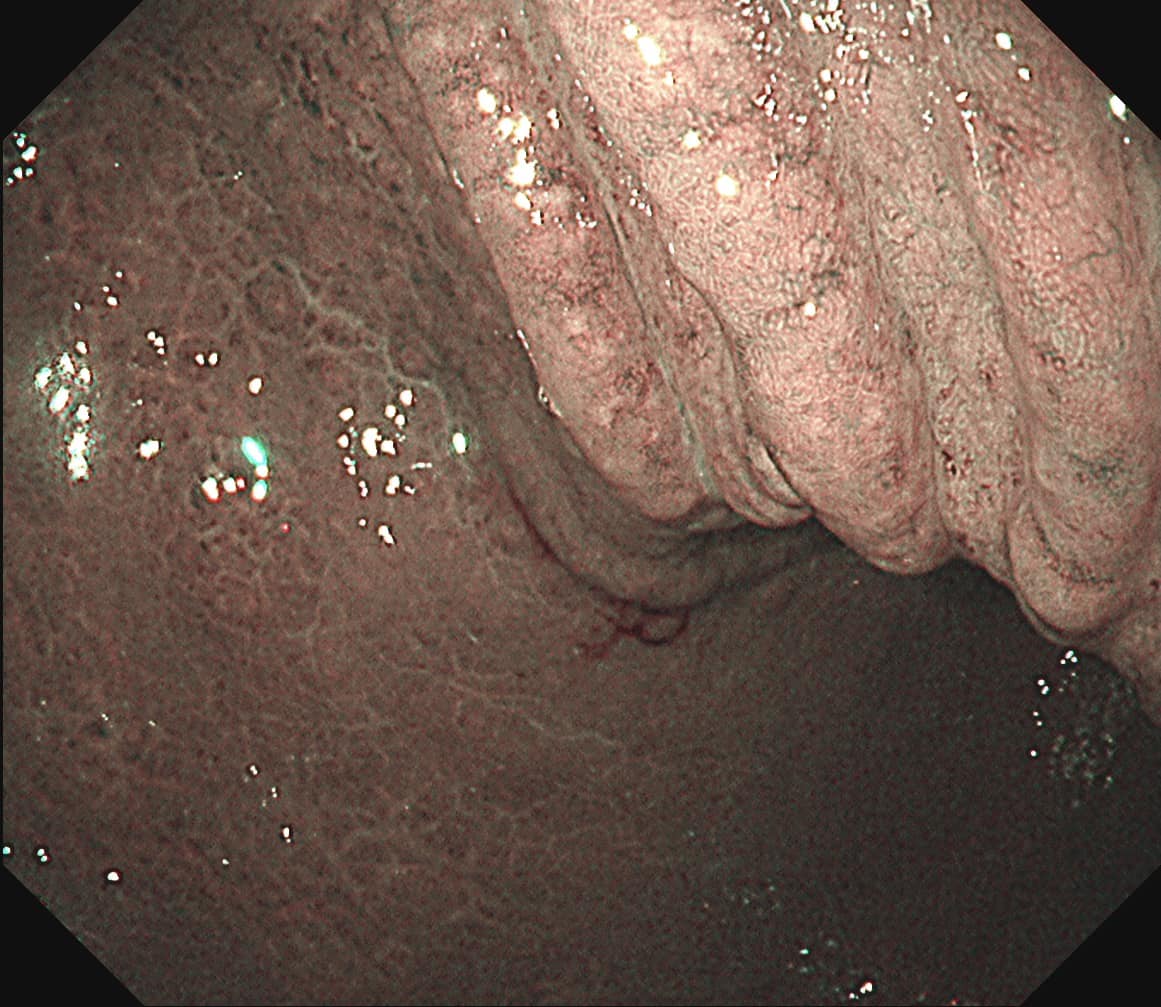

台北禾馨民權健康管理診所院長林相宏3月8日在臉書粉專《胰臟醫師 林相宏》分享「健檢的價值」,他提到曾有一名30歲女士來診所做身體檢查,照胃鏡時,雖未見腫瘤,但他眼尖發現病患的胃壁有許多小結節突起,他表示,「我喜歡形容成像『苦瓜表面』,或像『健康步道』」。

林相宏提高警覺,在仔細追問得知,患者沒有胃悶、胃痛、食慾體重下降、解黑便、火燒心等胃感染相關病症,只有偶爾脹氣、打嗝。林相宏認為事有蹊蹺,應該先做更深入的檢查,所以進一步安排強化內視鏡檢查,才發現患者的胃表面黏膜已出現不規則、類似龜裂的樣子,經切片診斷結果證實罹患低惡性度的淋巴瘤,亦「胃淋巴癌(MALToma)」。